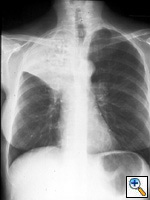

Fig. 12a:

Posterior-anterior chest radiograph shows right upper lobe bronchogenic carcinoma with associated lobar volume loss.